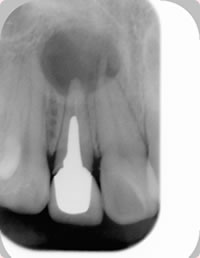

歯根嚢胞とは、歯根の先端部位に生じる袋状の病変のことをいいます。顎骨が吸収して嚢胞が大きくなるため、レントゲンでは黒く映ります(図1)。

図1 前歯にできた歯根嚢胞. 直径1センチほどの大きさになっている